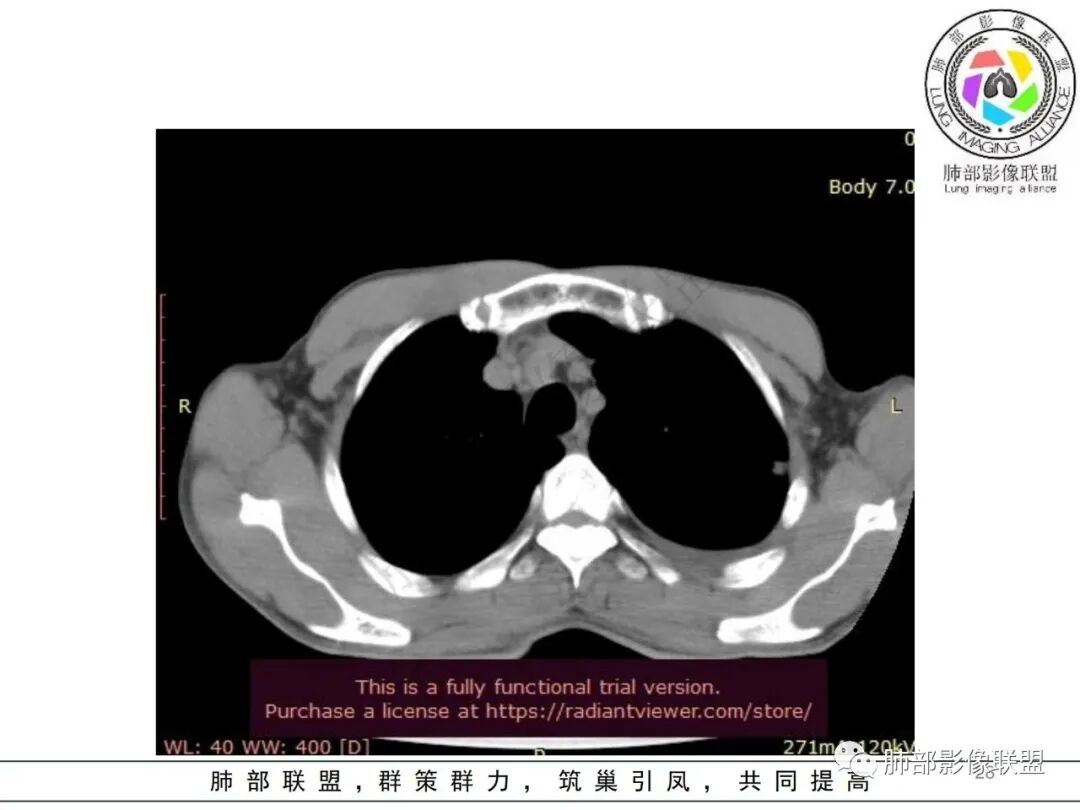

影像表现:双肺弥漫分布斑片影、实变影、磨玻璃影、结节影,晕征、反晕征,随机分布,部分病灶空洞形成前兆,左侧胸腔积液。

两肺多发斑片状实变影,周围GGO

主体还是沿支气管,大片叶段性分布

影像上急性感染,大叶性病变为主

单凭影像:鹦鹉热、军团要考虑,因为内部无坏死,非典型气道为主